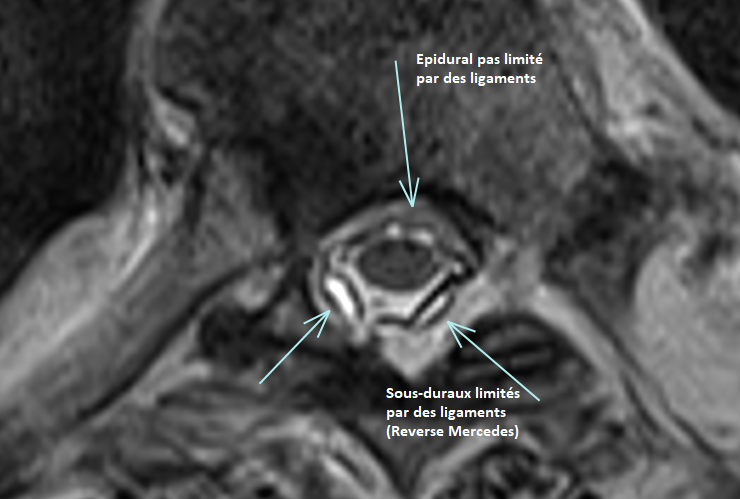

Hématome Epidural

Abcès Epidural

Kyste Synovial Epidural

- HyperT2 avec bords HypoT2